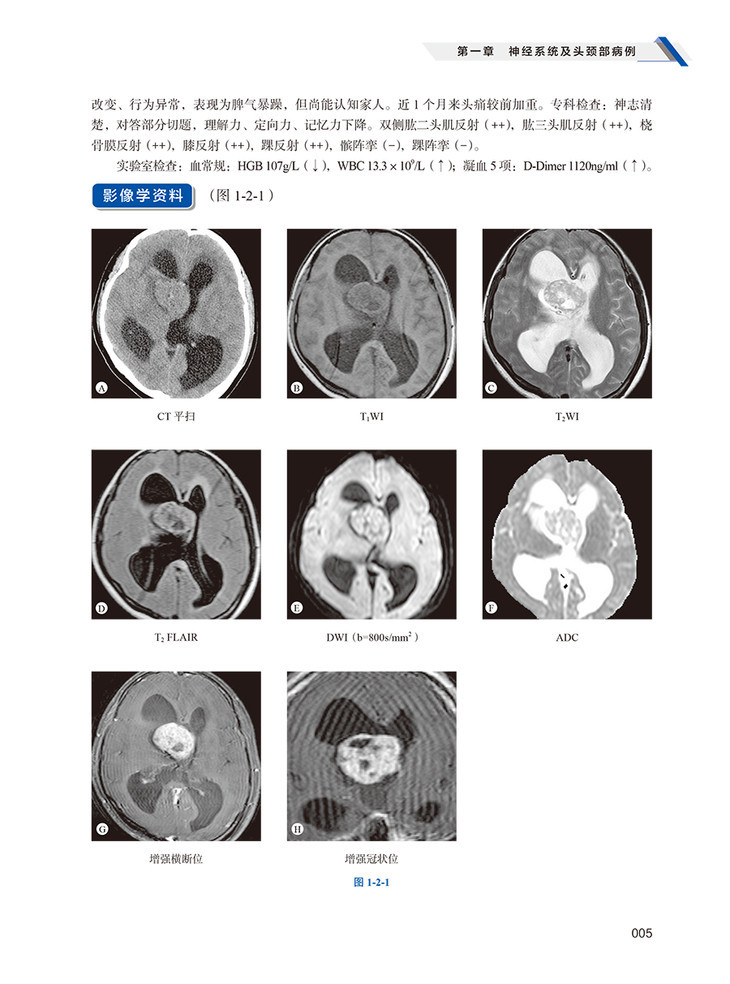

本书由广东省和陕西省放射专业规培基地联合编写。为贯彻国家住院医师规范化培训要求,进一步提升住培医师和青年医生临床技术水平,基于医学影像科日常工作中遇到的诸多疑难病例和误诊病例,结合放射专业住院医师规范化培训细则和青年医师影像诊断技能提升的需求,精心筛选出180例左右的疑难及误诊病例,指出疑难之处,剖析疑难原因,解析疑难要点,提出解析思路。依据住院医师规范化培训放射专业亚专科要求,将病例分为神经系统(含头颈部)、胸部(含呼吸、循环)、消化、泌尿生殖和骨肌关节五个部分,每个部分精心筛选约30~40个病例,分别进行临床资料、影像学检查、手术记录与病理、诊断思路分析、鉴别诊断要点梳理、文献回顾复习等部分进行详细论述。